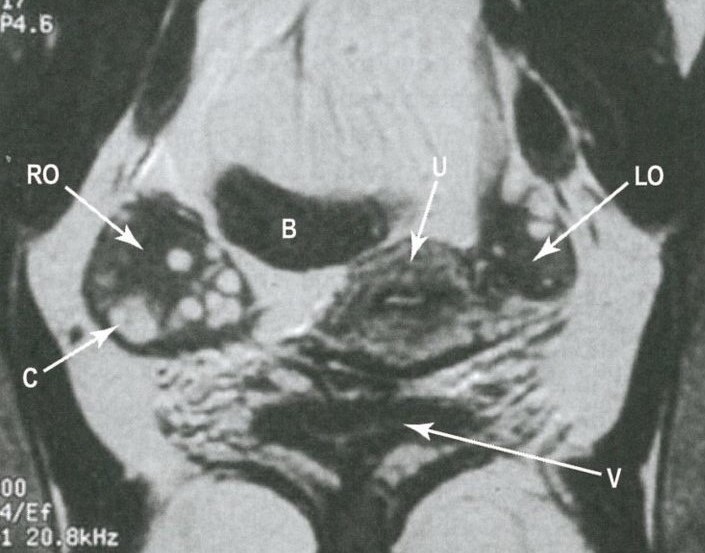

Kallmannov syndróm, olfaktogenitálny syndróm (anglicky Kallmann syndrome) je veľmi zriedkavé, geneticky podmienené vrodené ochorenie, ktoré sa častejšie vyskytuje u mužov ako u žien a má vplyv najmä na pohlavné dospievanie. Príčinou tohto ochorenia je mutácia niekoľkých génov, ktorá vedie k poruchám vývoja čuchového ústrojenstva a tiež k poruchám hypotalamu, čo je časť mozgu, ktorá je zodpovedná aj za správny pohlavný vývoj jedinca, ktorý je teda narušený. Príčina príznakov pozostáva v zníženej koncentrácii hormónov, ktoré ovplyvňujú vyplavovanie pohlavných hormónov a vývoj semenníkov a vaječníkov, teda bude znížená ich funkcia.

• hypogonadizmus - nedostatočný vývoj a porucha funkcie pohlavných žliaz (je znížená)

• retencia semenníkov - porucha zostupu semenníkov u chlapcov

• u dievčat nie je menštruácia

• porucha vývoja obličiek